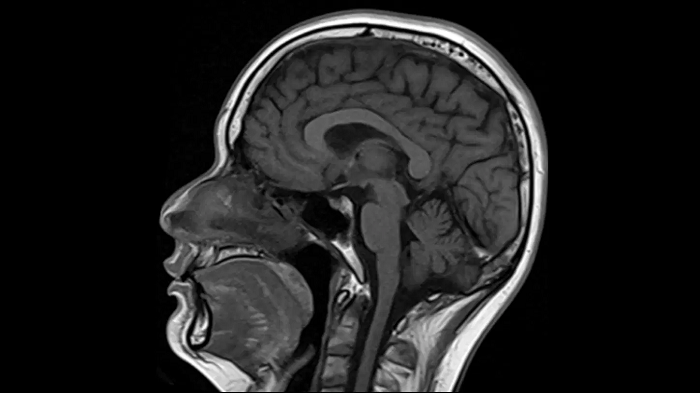

T1 SE

Outstanding T1 imaging with MAGNETOM Free.Star.

0.4 x 0.4 x 5.0 mm2

TA 2:38 minutes

MAC-ID: 7aaaa0195.